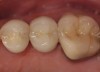

Case 2

A Class IIIN maxillary left second molar required restoration (Figure 6). Four canals, a chamber space, and little cross section of tooth structure were in the gingival third. Gutta-percha was removed with a Peeso reamer supplied in the C-1 kit. The canal was shaped with a bur in the kit, which was the same size as the corresponding post (Figure 7). The tooth structure was bonded with Brush & Bond™ (Parkell, www.parkell.com), and then the resin cement was spun into the canal with a lenticulo spiral. A C-1 white post was placed in the palatal canals (Figure 8). The C-1 White Post is a fiber-reinforced composite post, which flexes at the same rate as dentin to minimize root stresses.

Core build-up was completed with Absolute Dentin™ (Parkell, www.parkell.com) dual-cure high-strength core composite. There are variations on color and how materials cure. For example, Light-Core™ (Bisco, www.bisco.com) is a light-cured blue material, Encore® (Centrix, www.centrixdental.com) is a self-cure white material, and Para Core (Coltène Whaledent, www.coltene.com) is a dual-cure white or dentin-colored material. Material was placed directly and light-cured for 40 seconds (Figure 9). Final preparation for a PFM was completed (Figure 10). The final crown was placed (Figure 11).

Figure 6  Endodontically treated maxillary right second molar.

Figure 6

Figure 7  Second molar with the palatal canal prepared for post placement.

Figure 7

Figure 8  Second molar after post cementing.

Figure 8

Figure 9  Cure core material placed without a matrix.

Figure 9

Figure 10  Final tooth preparation to accept a PFM crown.

Figure 10

Figure 11  Final porcelain-fused-to-metal crown.

Figure 11